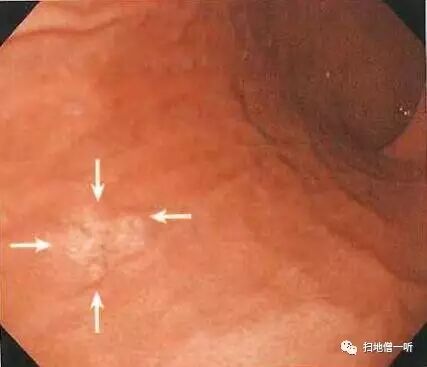

背景粘膜RAC阳性,提示HP未感染。穹隆部后壁可见一小片褪色粘膜,边界清晰,表面光滑,腺管扩张,伴随有蛇形血管。

• 胃底腺性胃癌表现为平坦的褪色病变,表面扩张伴随蛇形血管

• 内镜所见典型表现为SMT样扁平隆起型形态,退色调,表面扩张多伴蛇形树枝状血管。当表现为IIa型病变时与类癌相鉴别;当表现为IIb型病变时与淋巴瘤相鉴别。